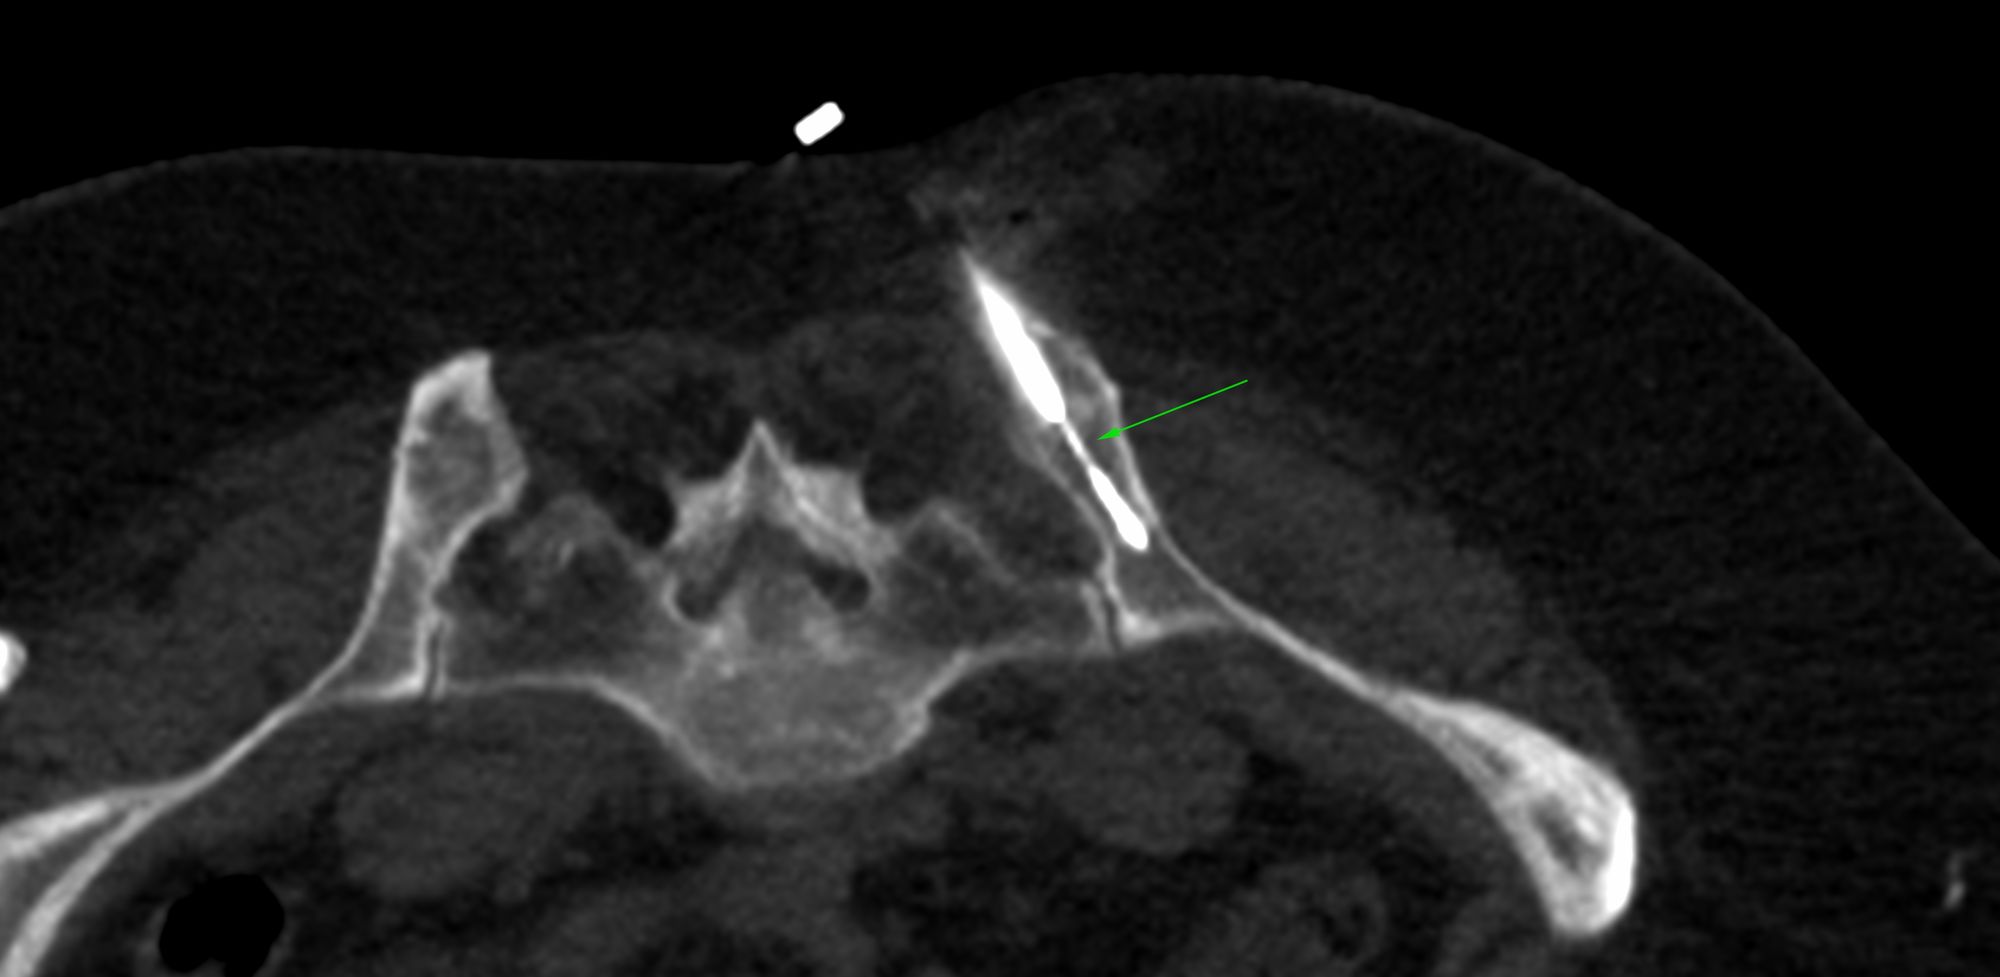

Case 11: D3 Spinal Transverse Process and Pedicle Biopsy